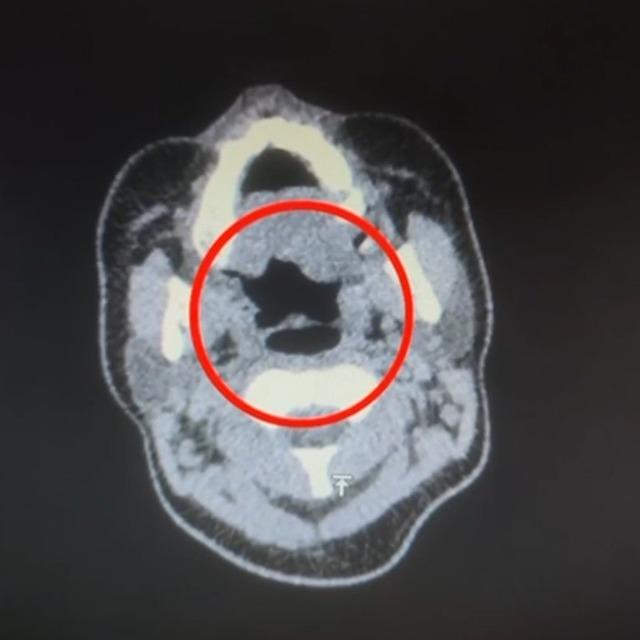

Kayseri İl Emniyet Müdürlüğü Narkotik Suçlarla Mücadele Şube Müdürlüğü ekipleri, uluslararası uyuşturucu madde ticareti yapan kurye şahıslara yönelik operasyon düzenledi. Operasyonda A.R.’yi (27) gözaltına alan ekipler, şahsı hastane muayenesine götürdü.

Şüphelinin yapılan iç beden muayenesinde, mide kısmında bulunduğu tespit edilen 50 adet kapsül şeklinde toplam 500 gram uyuşturucu madde ele geçirildi.